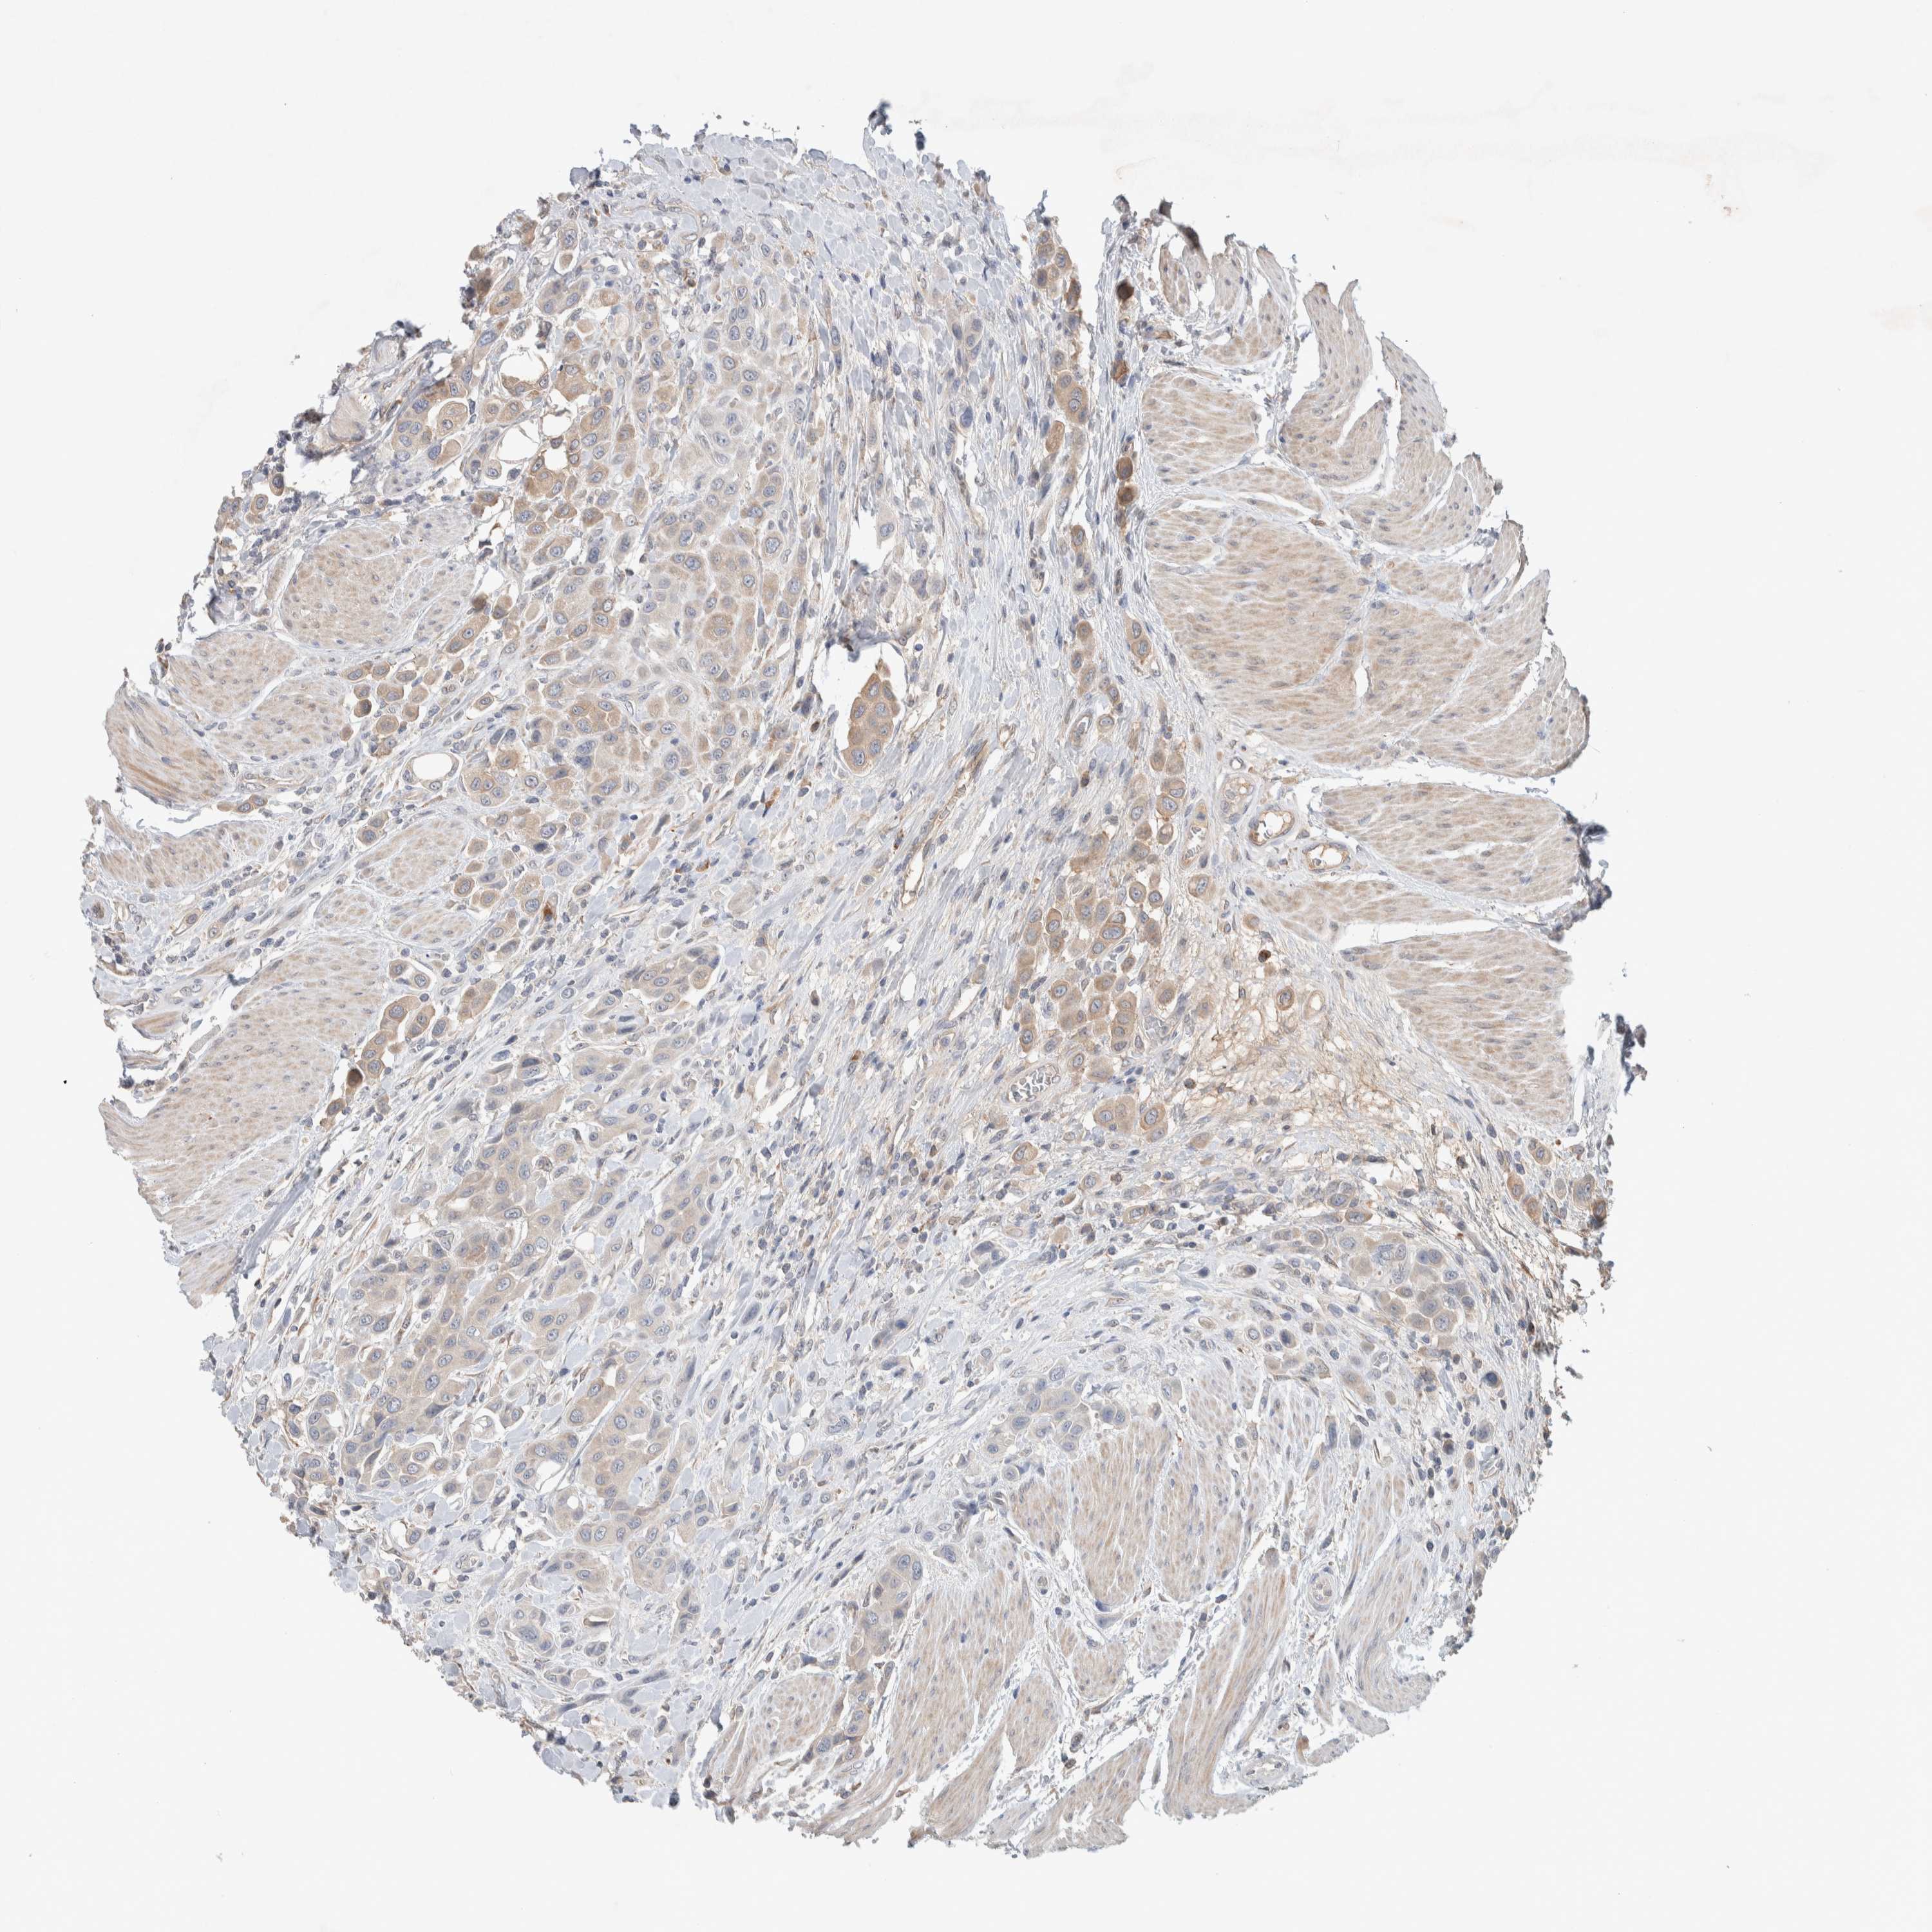

UROTHELIAL CANCER - Protein expressioni

A mouse-over function shows sample information and annotation data. Click on an image to view it in a full screen mode. Samples can be filtered based on level of antibody staining by selecting one or several of the following categories: high, medium, low and not detected. The assay and annotation is described here.

Note that samples used for immunohistochemistry by the Human Protein Atlas do not correspond to samples in the TCGA dataset.

Antibody stainingi

Antibody staining in the annotated cell types in the current human tissue is reported as not detected, low, medium, or high, based on conventional immunohistochemistry profiling in selected tissues. This score is based on the combination of the staining intensity and fraction of stained cells.

Each image is clickable and will lead to virtual microscopy that enables deeper exploration of all samples and also displays staining intensity scores, fraction scores and subcellular localization as well as patient and tissue information for each sample.

Antibody HPA023938

Antibody HPA023945

Antibody HPA024011

Antibody CAB020841

Staining

High

Medium

Low

Not detected

Intensity

Strong

Moderate

Weak

Negative

Quantity

>75%

75%-25%

<25%

None

Location

Nuclear

Cytoplasmic/membranous

Cytoplasmic/membranous,nuclear

Urothelial carcinoma, Low grade

Urothelial carcinoma, High grade